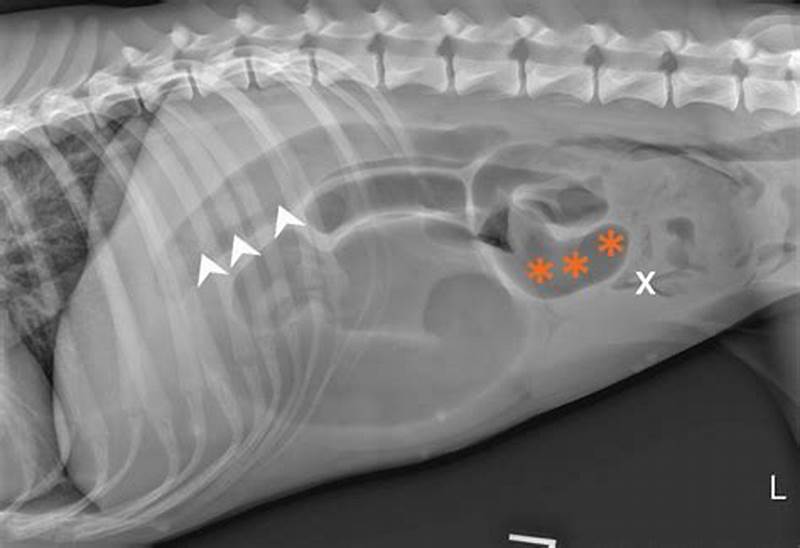

Abnormal Gas Pattern In Dogs